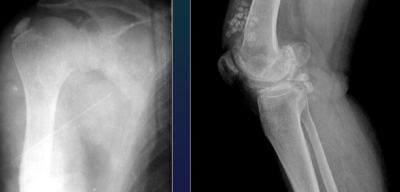

MSK Trauma Rof of Imaging

Positive Dg + lesion type

Monitoring + Dg complications

METHODS

CT (complex fractures)

Conventional Xray

Nuclear Medecine (sometimes)

Arthrography

Angiography (concomitant vascular involvement)

MRI (soft tissue, bone concussion)